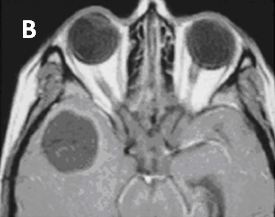

Hình 6. Hình ảnh u di căn não trên phim cộng hưởng từ T2 (A) và T1 sau tiêm thuốc của bệnh nhân ung thư tử cung. Tổn thương dạng tròn, không ngấm thuốc với tín hiệu dịch, có phù não xung quanh.